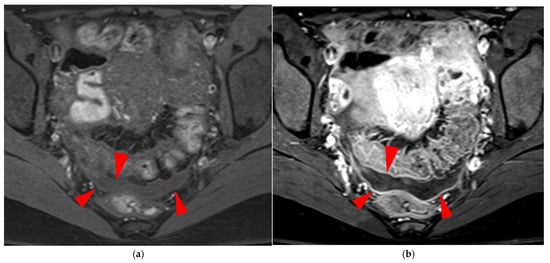

Figure 15. Pelvic MRI scan of a patient with a “kissing ovaries” sign and rectal involvement (i.e., HTD type 6 USLs). (a,b) Axial T2WI (a) and contrast-enhanced T1WI (b) show both ovaries in close proximity (“kissing ovaries” sign) (arrowheads) and rectosigmoid wall infiltration (arrows). (c) Sagittal contrast-enhanced T1WI shows rectosigmoid wall infiltration, appearing as a “medallion-shaped” lesion outlined by markedly enhancing mucosa (arrowhead).

2.3.1. “Kissing Ovaries”: A Form Straddling Between Type 5B and Type 6 USLs

Besides endometriomas, another type of ovarian involvement in DIE includes adhesions that cause the ovaries to retract medially across the midline, behind the uterus, into the pouch of Douglas. When the ovaries are displaced medially and are in close proximity, they are commonly referred to as “kissing ovaries”. Additionally, medialized ovaries on preoperative imaging expose the digestive tract to a 20% risk of involvement [22]. In our experience, the injection of a contrast agent is useful when there is doubt about an endometriotic rectosigmoid invasive lesion on T2WI, especially if a rectal filling was not performed. A markedly enhancing mucosa, which outlines rectosigmoid local wall thickening on post-contrast T1WI without fat suppression (forming a “medallion-shaped” lesion), is a valuable aid to diagnosis.

In the HTD MRI classification of USLs, the “kissing ovaries” sign is considered a form between types 5B and 6. In the case of concomitant rectal involvement, the USL is classified as type 6 (Figure 15); otherwise, it is classified as type 5B (comparable to a nodule with spiculated margins).